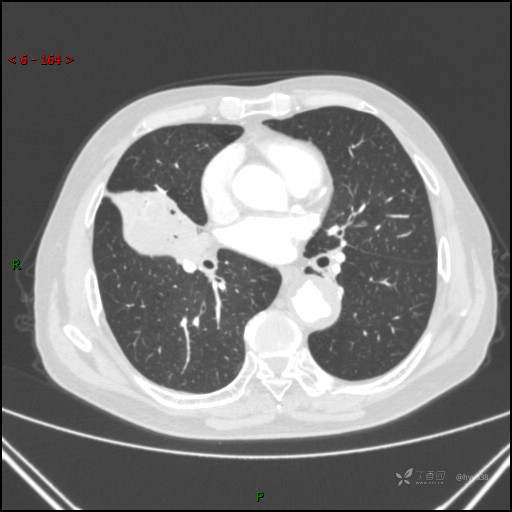

胸部CT肺窗